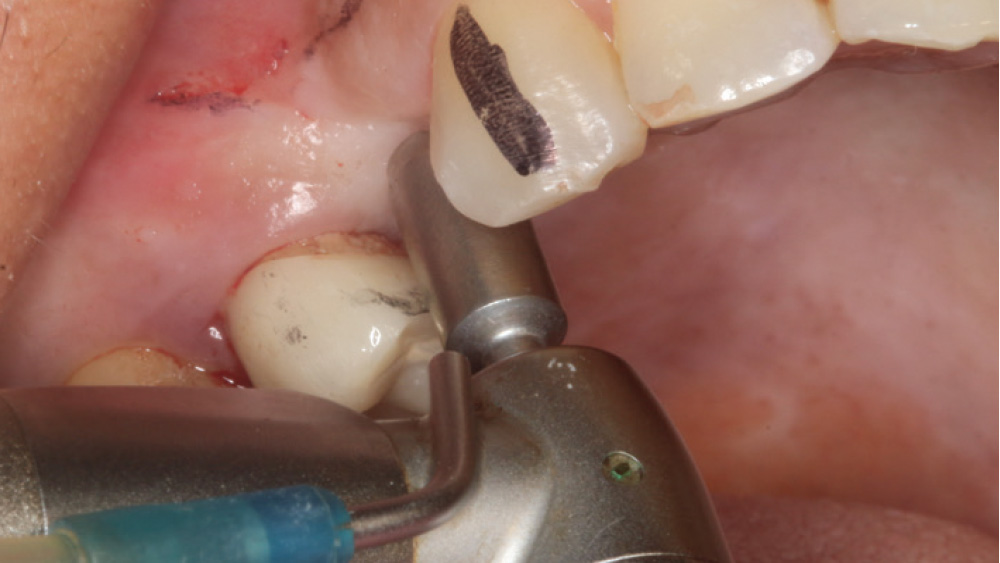

When the attached tissue is minimal, a flap procedure allows the surgeon to reposition the flap to create more attached gingiva and improve the interdental papillae at the implant site. Reflecting a gingival flap also enables the practitioner to more clearly see the final position of the implant at the crest of the bone. If it’s necessary to visualize the bone during the surgical procedure due to uncertain ridge width or height, flap reflection is the safest, most predictable approach.

In contrast, with a flapless procedure, a tissue punch is used to gain access to the bone through the gingiva, minimizing postoperative discomfort by eliminating incisions in the mucosal tissue. Whenever mucosal tissue is incised, prostaglandin and histamine are released, resulting in potential postoperative swelling and pain. Therefore, when there is an adequate width of attached gingiva on the facial aspect of an implant site, a flapless procedure may be indicated, eliminating any suturing requirements.

The following case, which I performed alongside Dr. Stephanie Tilley of Pensacola, Florida, illustrates the use of both surgical techniques for the same patient, who presented with edentulous spaces in the areas of both right and left maxillary first bicuspids. Due to varying soft-tissue volume on each side of the arch, implant surgery was performed using a flapless procedure for one site, while the attached gingiva was reflected to expose the available hard tissue for the other. As a result of proper site evaluation, treatment planning and restorative-driven implant placement, both surgical techniques led to successful outcomes for the patient.